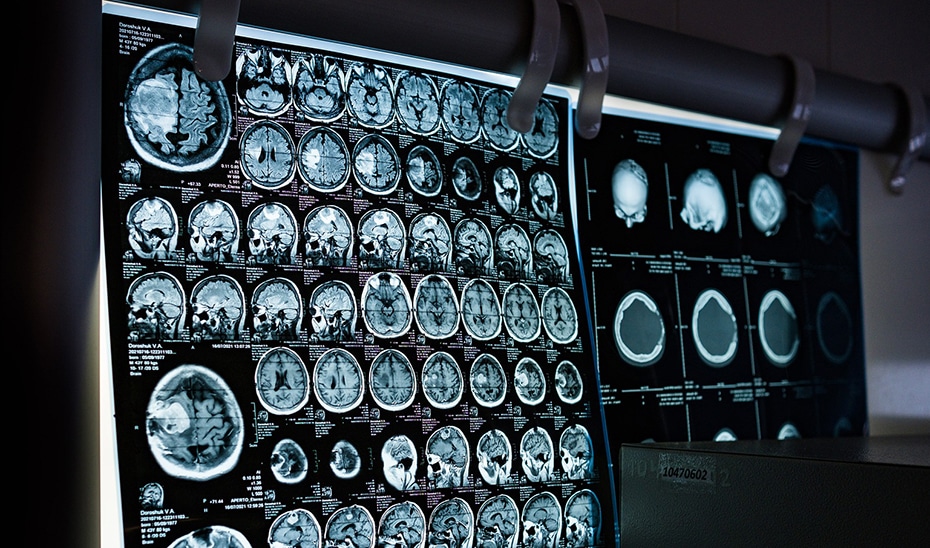

El glioblastoma, aunque poco frecuente, es altamente agresivo, con una incidencia de tres a cinco casos por cada 100.000 habitantes y una supervivencia media de 14 a 16 meses con los tratamientos actuales. El dispositivo utilizado, optune®, ya está aprobado en Estados Unidos y recomendado por entidades como la Sociedad Española de Oncología Médica. Su incorporación en Andalucía busca igualar las oportunidades de acceso a tratamientos innovadores con las mejores prácticas europeas.